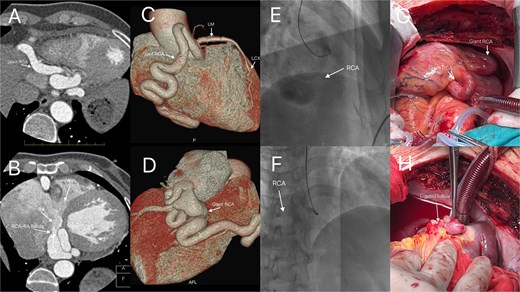

Following surgery, the patient was transferred to the intensive care unit (ICU) for further management. Upon ICU admission, the patient received continuous vasoactive agent infusion for blood pressure support, dexamethasone for edema reduction, protamine for heparin reversal, and cefazolin sodium (1 g) for antibiotic prophylaxis. Her postoperative course was stable, with transfer from the ICU on the following day. Follow-up CCTA showed no significant abnormalities (Fig. 3A and B). The patient was discharged on postoperative day 7. Upon discharge, the patient was prescribed a single antiplatelet regimen of aspirin (100 mg daily) to prevent thrombosis at the coronary arteriotomy and aneurysm repair sites, with careful consideration of bleeding risks. This medication plan was intended for adjustment according to subsequent imaging surveillance. Follow-up during the first postoperative year included scheduled CCTA and echocardiography every 3 months, alongside regular clinical visits.

Postoperative imaging on day 5 after surgical repair of a right coronary artery fistula with giant aneurysm. (A) Axial contrast-enhanced CT image at the level of the aortic root. The right coronary artery (arrow) demonstrates a normalized caliber and wall contour, with complete resolution of the preoperative aneurysmal dilation. (B) Volume-rendered three-dimensional CT reconstruction (anterolateral view). The reconstruction focuses on the course of the right coronary artery (arrow), which exhibits a smooth, uniform, and patent lumen without evidence of the previous aneurysm or fistula.